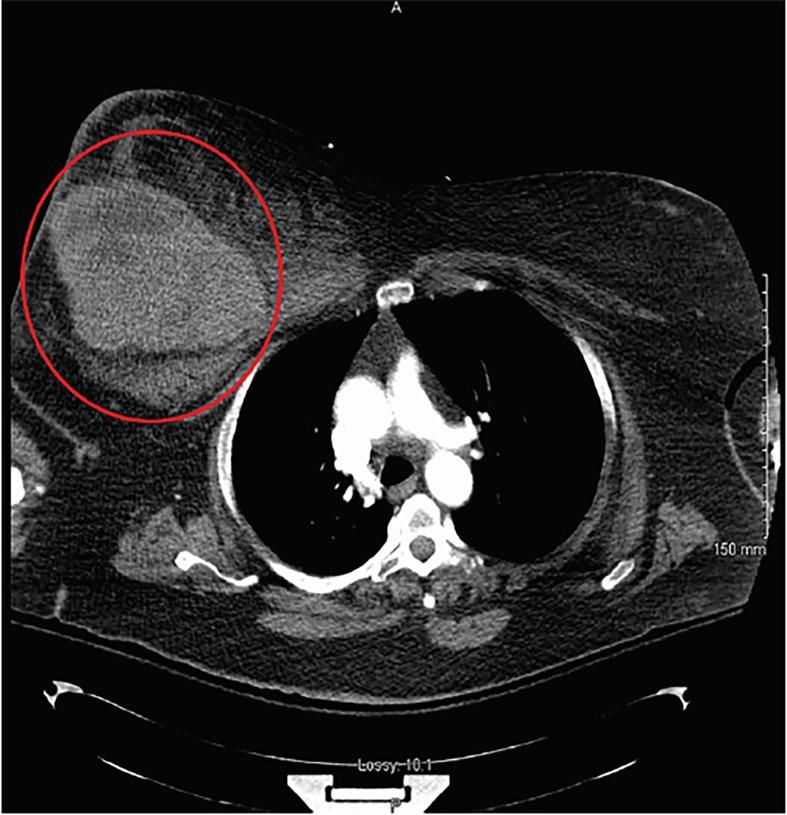

Massive Right Breast Hematoma.